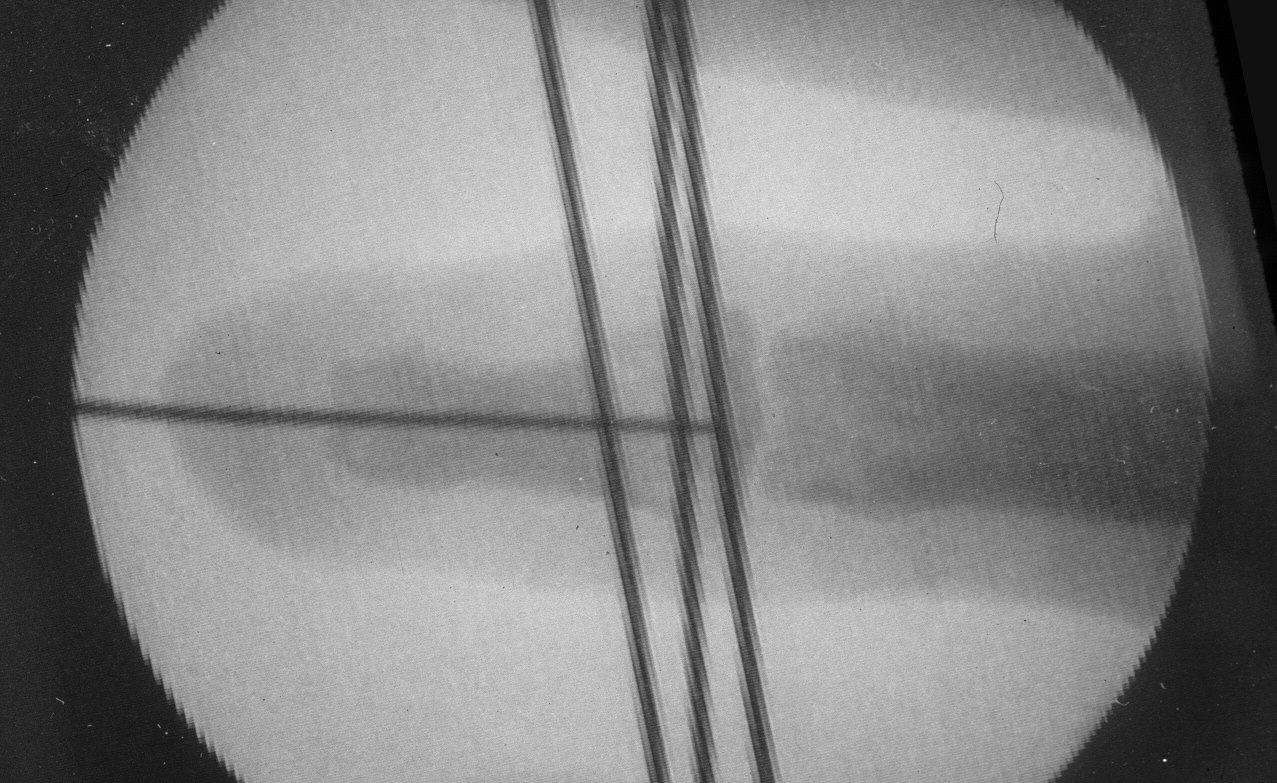

Case 2. Middle phalanx lengthening with proximal metaphyseal osteotomy, distraction and bone graft:

Image Image